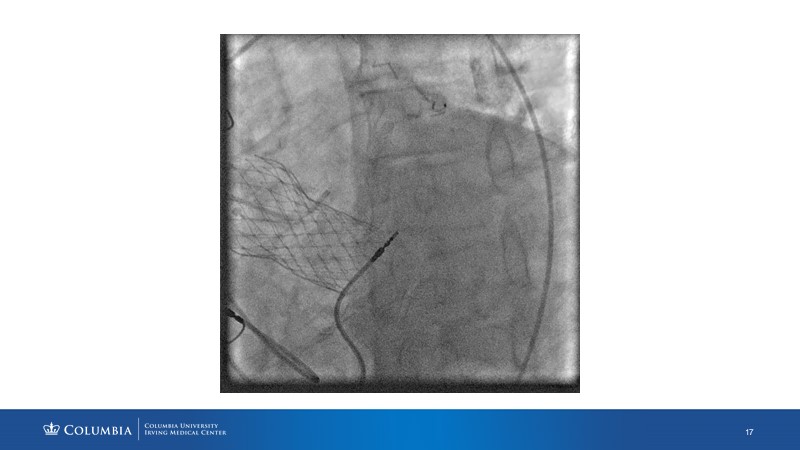

Through the presentation of real-life clinical cases, this session will allow you to discover the use of ALLEGRA for valve-in-valve TAVI, understand the management of coronary artery disease in TAVI patients, better detect when and how to protect coronary arteries during TAVI, or even learn how to perform commissural alignment with ALLEGRA.

- To better detect when and how to protect the coronary arteries during TAVI